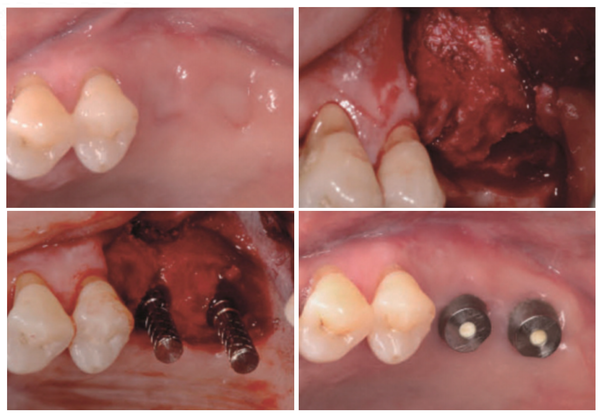

2003년부터 덴티움 임플란트만을 사용해 온 한승민(서울이촌치과) 원장은 덴티움의 ‘Bright Implant’ 를 활발히 사용하고 있다.

한 원장은 “‘Bright Implant’는 그동안 높은 성공률과 안정성을 인정받은 덴티움의 제품군과 같은 임플란트 표면처리라 믿음이 생겼다. 무엇보다 주목한 것은 디자인과 픽스처-어버트먼트 커넥션의 변화”라고 밝혔다.

한 원장에 따르면 “‘Bright Implant’는 디자인 측면에서 픽스처 자체의 Taper 정도를 줄였으면서도 초기 고정력 확보의 장점을 잃지 않았다는 것이다. 그러면서도 수술 과정은 좀 더 술자 친화적으로 바뀌어 Counter Sink 과정 없이도 임플란트가 덜 들어가거나 Hard Bone에 밀려 기울어져 버리는 현상이 확연히 개선됐다”고 언급했다.

그는 “Microthread 없이 Macrothread만 채택하고, Thread의 간격도 Superline보다 조금 더 넓어졌다”면서 “식립을 좀 더 쉽게 하려는 의도가 어느 정도 성공한 것 같다”고 평가했다.

아울러 “기존 제품이 2.5mm Connection Depth 를 갖는데 비해 ‘Bright Implant’는 3.7mm로 Deep Connection을 갖는다”면서 “픽스처 어버트먼트의 접촉면적이 Superline군보다 50% 이상 증가됐다고 하는데, 이는 Joint Stability에 더욱 유리하게 작용할 것”이라고 밝혔다.